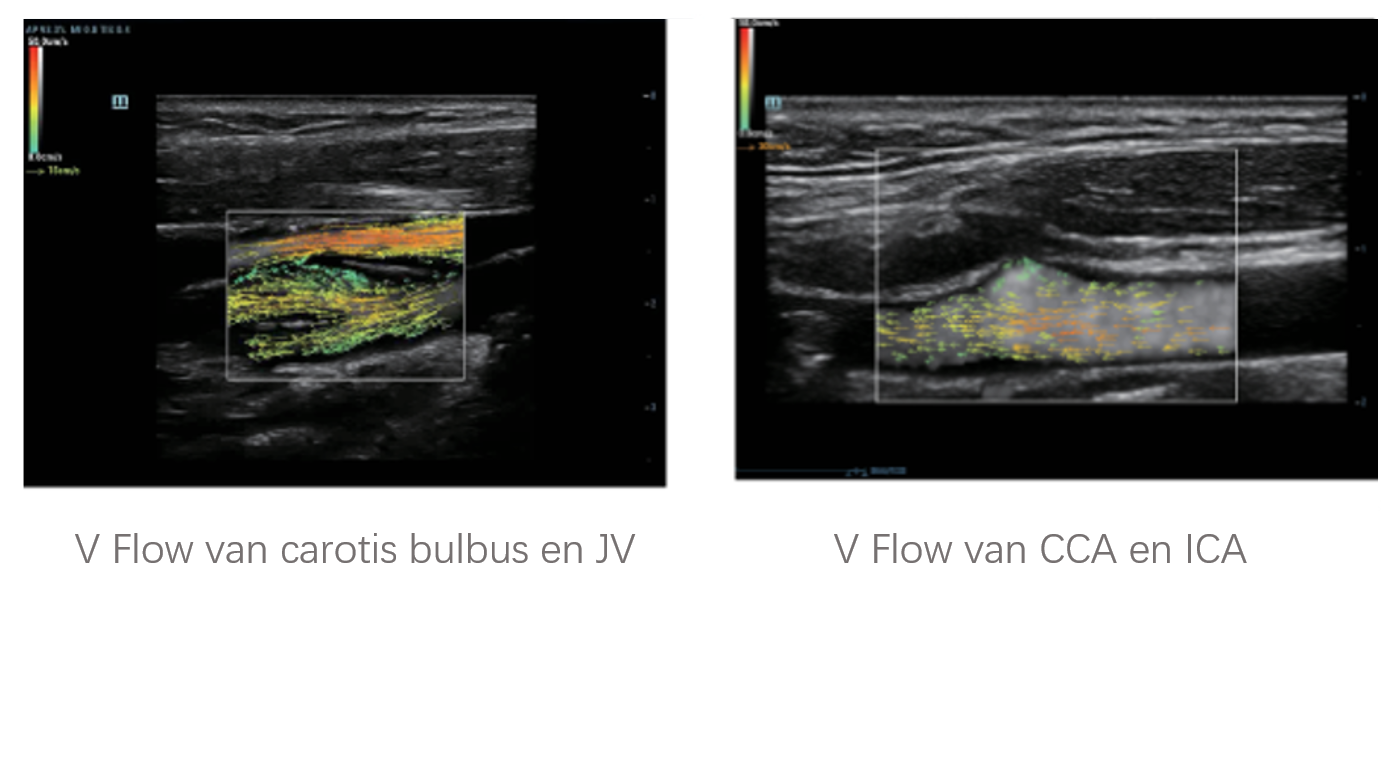

Naast de hoogwaardige beeldvormingskwaliteit verbetert de Resona 7 tevens de klinische onderzoeksmogelijkheden met de revolutionaire V Flow voor vasculaire hemodynamische evaluatie, en de intelligentste vlakacquisitie van een 3D-gegevenssets voor de diagnose van het foetale, centrale zenuwstelsel. Met zijn combinatie van de meest intu?tieve, op vingerbewegingen gebaseerde multi-aanrakingsbediening en alle essenti?le klinische functies loopt de Resona 7 voorop in de nieuwe golven van ultrasoundinnovatie.